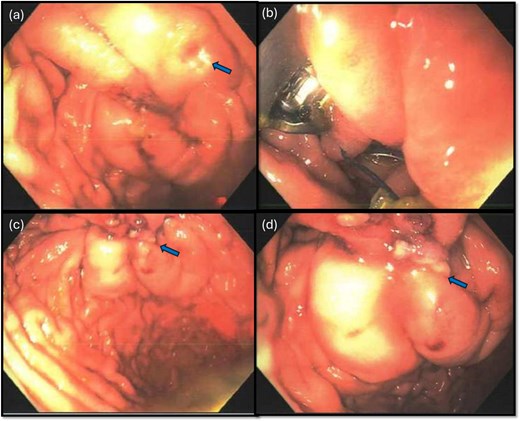

The gastroenterology team performed concurrent endoscopy using. With air insufflation and transillumination, a small pinpoint perforation was clearly identified on the anterior surface of the gastric-antrum (Figs 2 and 3).

Endoscopic view of the perforation. The picture in (a) demonstrates the site of the perforation. The picture in (b) shows the use of the overstitch technique to perform the closure endoscopically. Pictures (c) and (d) demonstrate the area of perforation once the first and second layers of endoscopic closure are completed, respectively.

To aid endoscopic visualization of the small perforation, a Maryland grasper was gently inserted into it (Fig. 2); the grasper’s tip, visualized endoscopically, confirmed the exact location. The remainder of the esophagus, stomach, and duodenum appeared normal. The Overstitch™ endoscopic-suturing device, mounted on a double-channel therapeutic endoscope and utilizing a tissue-helix for full-thickness bites, was used. Three full-thickness inverted figure-of-eight 2–0 Prolene sutures were placed at the perforation. Laparoscopic visualization confirmed full-thickness suture placement before the sutures were cinched, effectively closing the gastric wall defect (Fig. 3).